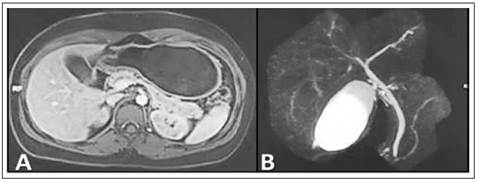

Tras el alta, retornó a Perú, donde se realizó una colangiorresonancia magnética contrastada, que mostró signos de proceso inflamatorio pancreático y peripancreático, derrame pleural laminar bilateral, así como resaltó la ausencia de colelitiasis o barro biliar, el árbol biliar de aspecto conservado, sin dilatación coledociana y ausencia de líquido libre en cavidad abdominal (Figura 2). Inmediatamente se realizó, de forma complementaria, una ecoendoscopía diagnóstica, donde se hallaron signos compatibles de pancreatitis aguda residual en la cola del páncreas, la presencia de un balón intragástrico también destacó que la vesícula y la vía biliares extrahepáticas se mostraron de aspecto conservado, sin presencia de litiasis en todo su trayecto (Figura 3).

Figura 2 Resonancia magnética de abdomen superior. A) Fase T1 con contraste, muestra aumento del tamaño del páncreas, alteración de la señal en toda su extensión y en la grasa peripancreática. B) Colangiorresonancia, vesícula biliar normal, sin presencia de imágenes litiásicas o barro biliar; colédoco (4,5 mm) y conducto pancreático principal, de aspecto y calibre habitual.

En un meta-análisis reciente de 7 estudios que incluyeron 2152 pacientes, el balón intragástrico Elipse demostró ser seguro y efectivo (disminución del IMC, circunferencia de cintura y triglicéridos), así como probó ser tolerable y con un mayor perfil de seguridad en comparación a otros dispositivos similares; dentro de los efectos adversos descritos son el dolor abdominal (37,5%), vómitos (26,9%), diarrea (15,4%) y obstrucción del intestino delgado (0,5%), aunque no se describieron casos de pancreatitis 12. Dentro del resto de modalidades de balón intragástrico, las complicaciones más comunes asociadas son: dolor abdominal, obstrucción del tracto de salida gástrico, náuseas, vómitos recurrentes, erosión esofágica y gástrica, perforación gástrica, neumonía y laringoespasmo. La pancreatitis ha sido descrita inicialmente de manera incidental, aunque ha cobrado mayor protagonismo en la última década probablemente asociado a una mayor masificación de dicho procedimiento endoscópico 1,5. En nuestra paciente se realizaron estudios básicos sobre la etiología del cuadro de pancreatitis, para lo cual, la ecoendoscopía es considerada el mejor método de imagen para descartar causas de origen biliar (barro biliar) o alteraciones estructurales en la glándula 13,14. No se consideró la etiología autoinmune debido a que los estudios de imagen transversal (tomografía abdominal y resonancia magnética) mostraron características típicas de la compresión del balón sobre el cuerpo y cola pancreáticos, siendo estos hallazgos compatibles con la llamada "pancreatitis por balón" 15. En la literatura la mayoría de los casos son de evolución leve, aunque se ha descrito necrosis pancreática y presencia de colecciones peripancreáticas, asociados a potenciales secuelas 7.